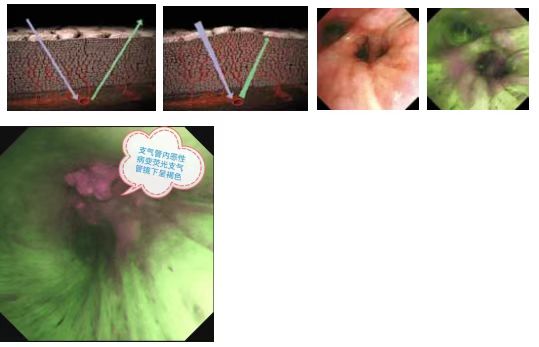

阳江地区医院首条奥林巴斯自体荧光成像(AFI)支气管镜

通过照射激励光 (390 至 470nm),观察胶原蛋白等荧光物质发出的自体荧光,波长 (540 至 560nm) 的光被循环血红蛋白吸收,正常组织区域成绿色,不典型增生、原位癌会产生红色荧光和更弱的绿色荧光而表现为红色或红棕色。自体荧光非常微弱,常规的 CCD 很难捕获,奥林巴斯PF-260荧光支气管镜采用了高灵敏度的 CCD,可实现清晰稳定的图像,以精细、清晰、高对比度的图像突出显示炎性和肿瘤组织,从而轻松地区分正常和异常组织,及早检出癌性和癌前病变,以及侵犯的范围,争取早期根治的机会。